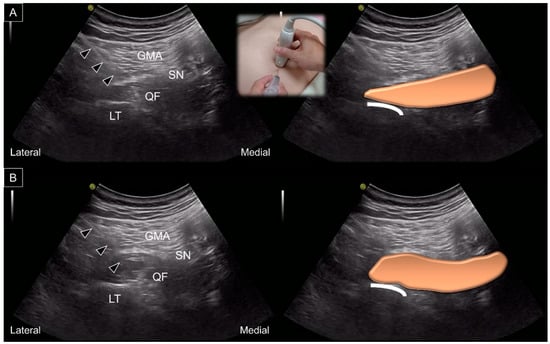

8. Dynamic Ultrasound Evaluation

9. US-Guided Intervention